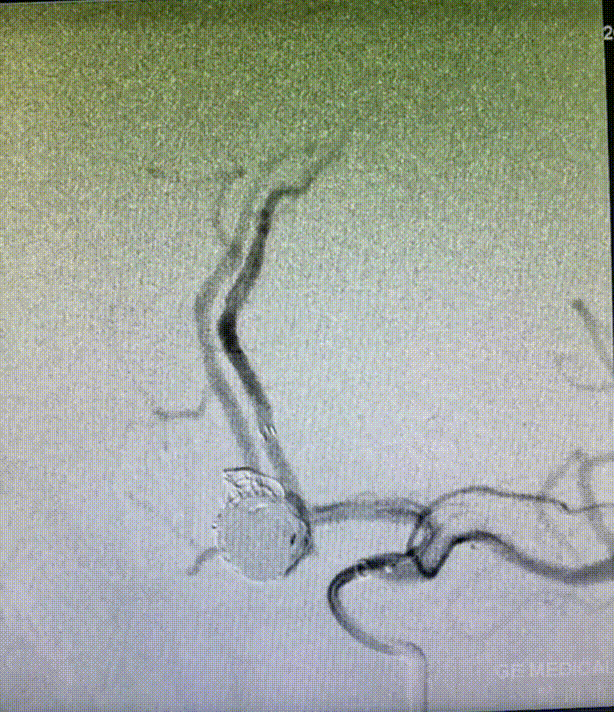

术后造影:弹簧圈致密填塞。

栓塞后造影:动脉瘤致密填塞。